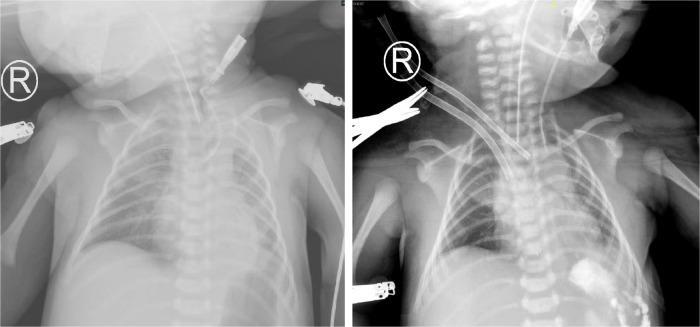

先天性膈疝新生儿术后心肺衰竭的体外膜肺氧合成功应用:病例报告及文献综述

Successful extracorporeal membrane oxygenation for postoperative cardiopulmonary failure in newborns with congenital diaphragmatic hernia: case reports and literature reviews.

INTRODUCTION

Congenital diaphragmatic hernia (CDH) is a structural defect caused by inadequate fusion of the pleuroperitoneal membrane that forms the diaphragm, allowing peritoneal viscera to protrude into the pleural cavity. Up to 30% of newborns with CDH require extracorporeal membrane oxygenation (ECMO) support. As with all interventions, the risks and benefits of ECMO must be carefully considered in these patients. Cardiopulmonary function has been shown to worsen rather than improve after surgical CDH repair. Even after a detailed perioperative assessment, sudden cardiopulmonary failure after surgery is dangerous and requires timely and effective treatments.

Three cases of cardiopulmonary failure after surgical CDH treatment in newborns have been reported. ECMO support was needed for these three patients and was successfully discontinued. We report our treatment experience.

ECMO is feasible for the treatment of postoperative cardiopulmonary failure in newborns with CDH.

先天性膈疝(CDH)是一种由于构成膈肌的胸腹隔膜融合不全导致的结构缺陷,使得腹腔脏器突入胸腔。高达30%的先天性膈疝新生儿需要体外膜肺氧合(ECMO)支持。与所有干预措施一样,必须在这些患者中仔细权衡ECMO的风险和益处。已表明先天性膈疝手术修复后心肺功能会恶化而非改善。即使经过详细的围手术期评估,术后突然发生的心肺衰竭也很危险,需要及时有效的治疗。

报告了3例新生儿先天性膈疝手术后发生心肺衰竭的病例。这3例患者均需要ECMO支持,且成功撤机。我们报告了我们的治疗经验。

ECMO对于治疗先天性膈疝新生儿术后心肺衰竭是可行的。